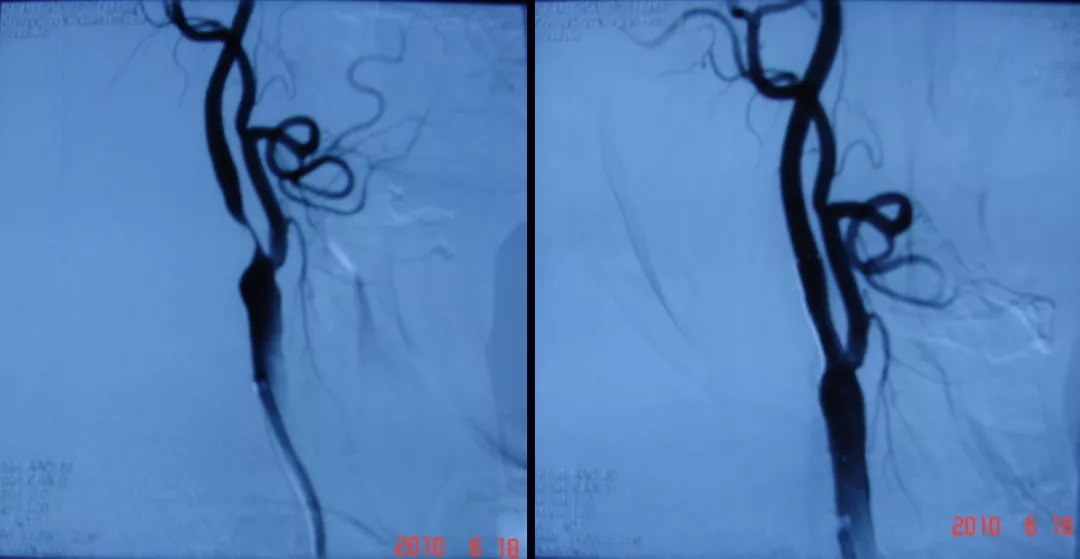

河池市人民医院开展的颈动脉支架植入术前后